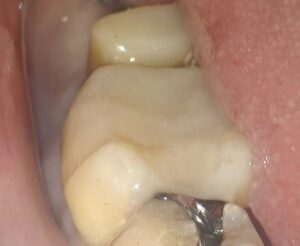

銀歯を外しました。

中の白くなっているところは土台の材料です。

この奥に虫歯がひろがっているため、この部分も除去します。

するとピンク色の材料が出てきました。

これはもともと神経があった穴に詰める材料で、以前の治療で詰められているものです。

その周りのドロドロしているところが虫歯であり、

残らず切削していく必要があります。

虫歯を切削している時の写真です。

親知らずとの間の炎症を起こした歯ぐきが露出しており、出血してきています。

これ以上奥の虫歯を削っていくとやがて骨が出てきます。